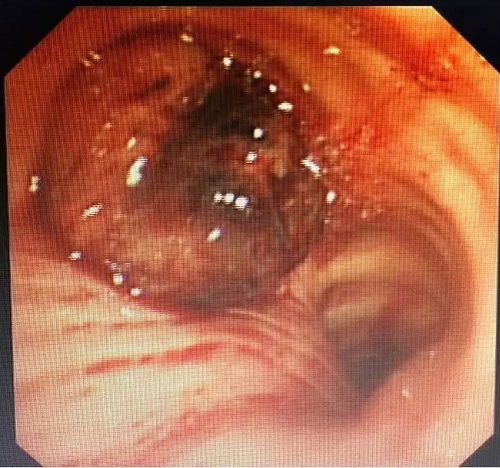

做好充分的术前准备后,在呼吸与危重症医学科主任姜淑娟的指导下,副主任医师龙飞、主治医师王永刚为患者进行手术。气管镜下发现,肿瘤表面血供非常丰富,表面渗血明显,且肿瘤已经越过隆突部分阻塞右主支气管和气管下段。这些表现明确解释了患者术前反复咯血和呼吸困难原因。

根据术前制定的手术方案,主刀医师应用高频电刀和氩气刀等热消融技术反复对肿瘤行消融治疗。经过1个多小时治疗,切除大部分肿瘤,局部肿瘤根部应用氩气刀止血和消融治疗。